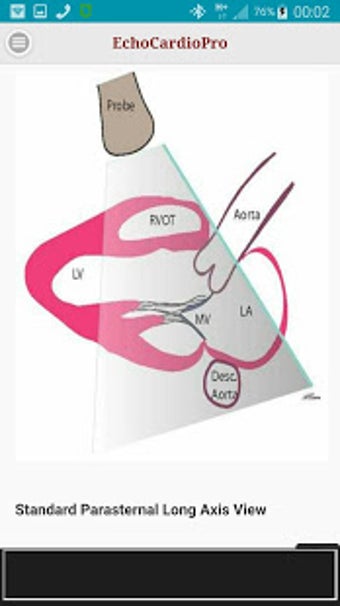

Aplikacja dostarcza kompleksowych informacji na temat echokardiografii przezklatkowej (TTE) i echokardiografii przełykowej (TEE) oraz ich odpowiednich korzyści w ocenie czynności skurczowej i rozkurczowej lewej i prawej komory, regionalnego ruchu ściany, wad zastawkowych serca i chorób osierdzia. Zawiera również szczegółowe informacje na temat różnych widoków, takich jak długoosiowy przysercowy, krótkoosiowy przysercowy, wierzchołkowy, podżebrowy, nadobojczykowy, śródprzełykowy, poprzezżołądkowy, głęboko poprzezżołądkowy i wysoko przełykowy.